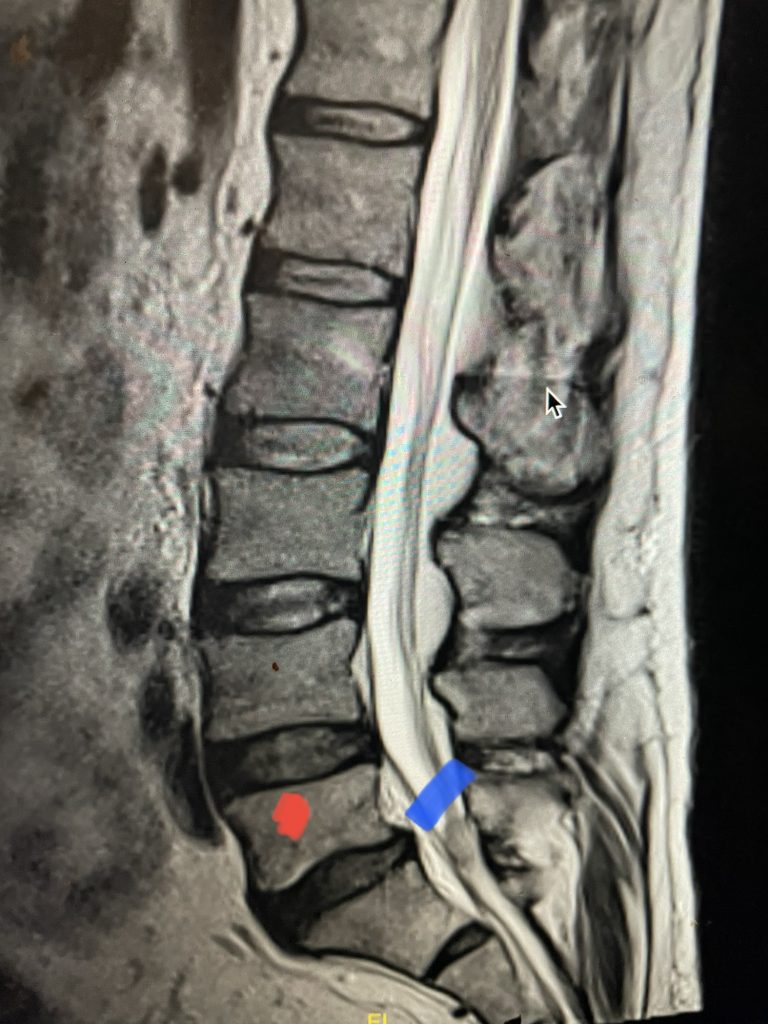

Fig 2: Sagittal T2-weighted MRI of the lumbar spine demonstrating a dysmorphic, trapezoidal-shaped L5 vertebral body (red dot) and a subtle grade 1 spondylolisthesis L5-S1 (blue line).

Fig 3: Sagittal CT scan with bone windows demonstrating an L5 pars defect (blue dot) and abnormal L5-S1 facet complex as well as a normal right pars structure of L5 (red dot).

Another interesting 54-year-old patient presented with low back pain and severe left lower extremity pain over two months. He had a history of falls. The pain in the leg was more bothersome to the patient. The patient had a work-up with an MRI and CT of the lumbar spine. MRI demonstrated a subtle grade 1 spondylolisthesis L5-S1 with a dysmorphic L5 vertebral body (Fig 2). There was a suggestion of a left L5 spondylolysis or defect in the bridge of bone that connects the superior facet process of the segment and the inferior facet process. A CT of the lumbar confirmed this unilateral abnormality which certainly could account for the patient’s left leg pain (Fig 3). This is an unusual finding in that most patients have bilateral pars defects. Patients with L5-S1 often have congenital abnormalities of the lumbosacral junction including weird shaped, elongated or dysplastic facet joints. A subtle L5-S1 spondylolisthesis with an associated smaller and misshapen L5 vertebral body is often associated with L5 spondylolysis. In addition, with a dysmorphic L5 vertebral body, there is secondary disc degeneration at L5-S1 and sometimes at the L4-5 disc with an associated retrolisthesis at L4-5. There is less surface to surface contact of the L4-5 and L5-S1 leading to chronic segmental instability.